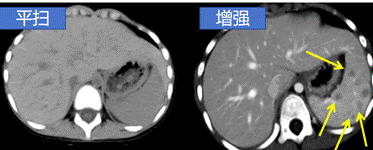

CT 增强是在 CT 平扫 的基础上,通过静脉注射含碘的造影剂,让血管、脏器、肿瘤等组织在影像上显示更清晰的一种检查方式。

✅ 病灶鉴别力强:能更好地区分炎症、肿瘤、囊肿

✅ 动态观察:动脉期、静脉期、延迟期多阶段成像,帮助医生全面分析